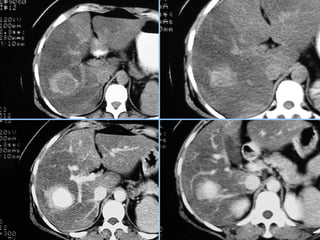

Hemangioma

 Fase art.      Fase portal    Fase tardia

 S/C              Fase art.

 Fase portal      Fase tardia

 S/C      Fase art.    Fase tardia

► s/c: Lesões bem definidas, lobuladas, hipodensas ao parênquima e

isodensas aos vasos intra-hepáticos.

► c/c: (aspecto típico em lesões 2-10cm):

 Fase arterial: Realce periférico nodular e descontínuo, com áreas

nodulares ou globuliforme, da periferia para o centro da lesão. Centrípeto.

 Fase portal: Realce progressivo e centrípeto (da periferia para o centro).

 Fase tardia: Ocorre o preenchimento completo e homogêneo da lesão, com

realce persistente.

► Tempo de enchimento completo depende do tamanho da lesão

► Lesões pequenas (<2cm): enchimento completo rápido

► Lesões grandes (>10cm): preenchimento incompleto da lesão (presença

de trombos, áreas de fibrose e/ou necrose).